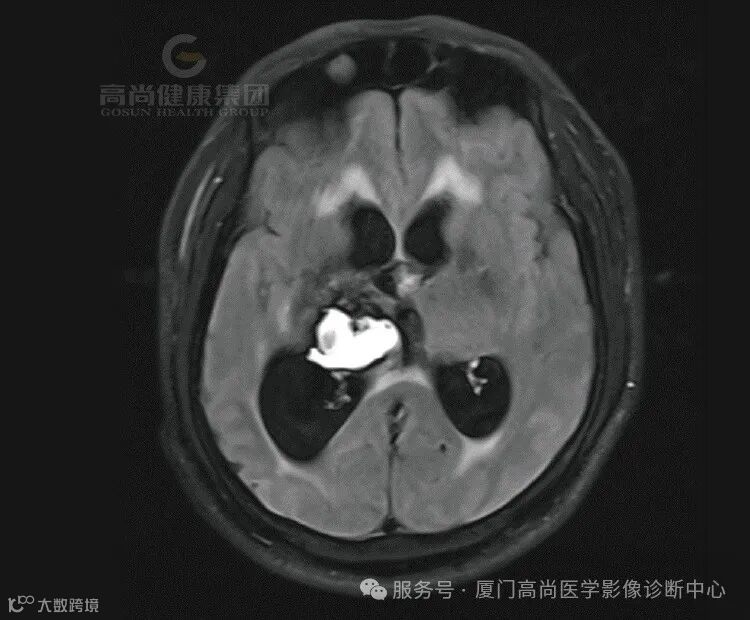

1.右侧丘脑、基底节、放射冠区病灶,考虑脑出血(亚急性期)并破入右侧脑室,中线结构局部左偏,请结合临床。

2.右侧额叶团状稍高异常信号影,相邻右侧额骨局部孔状影,请结合临床,建议复查。

(2)亚急性晚期(1-4周):T1和T2上均呈高信号,灶周水肿,占位效应逐渐减轻。

在MRI 上血肿周围脑水肿呈 TIWI 低信号、T2WI高信号,血肿周围脑水肿一般在发病后3~4d至第1周末最显著,以后逐渐减轻。约1个月后血肿开始消退。一般在2个月左右进入囊变期,此时血肿完全吸收,周围水肿完全消失,原血肿变为脑脊液的囊腔,即软化灶(T1WI呈低信号,T2WI呈高信号),与此同时出现邻近脑室、脑沟增宽等萎缩性改变。数月或更长一段时间后,可仅残存窄带状或局灶性小囊腔,小血肿甚至可完全被胶质瘢痕代替而消失。